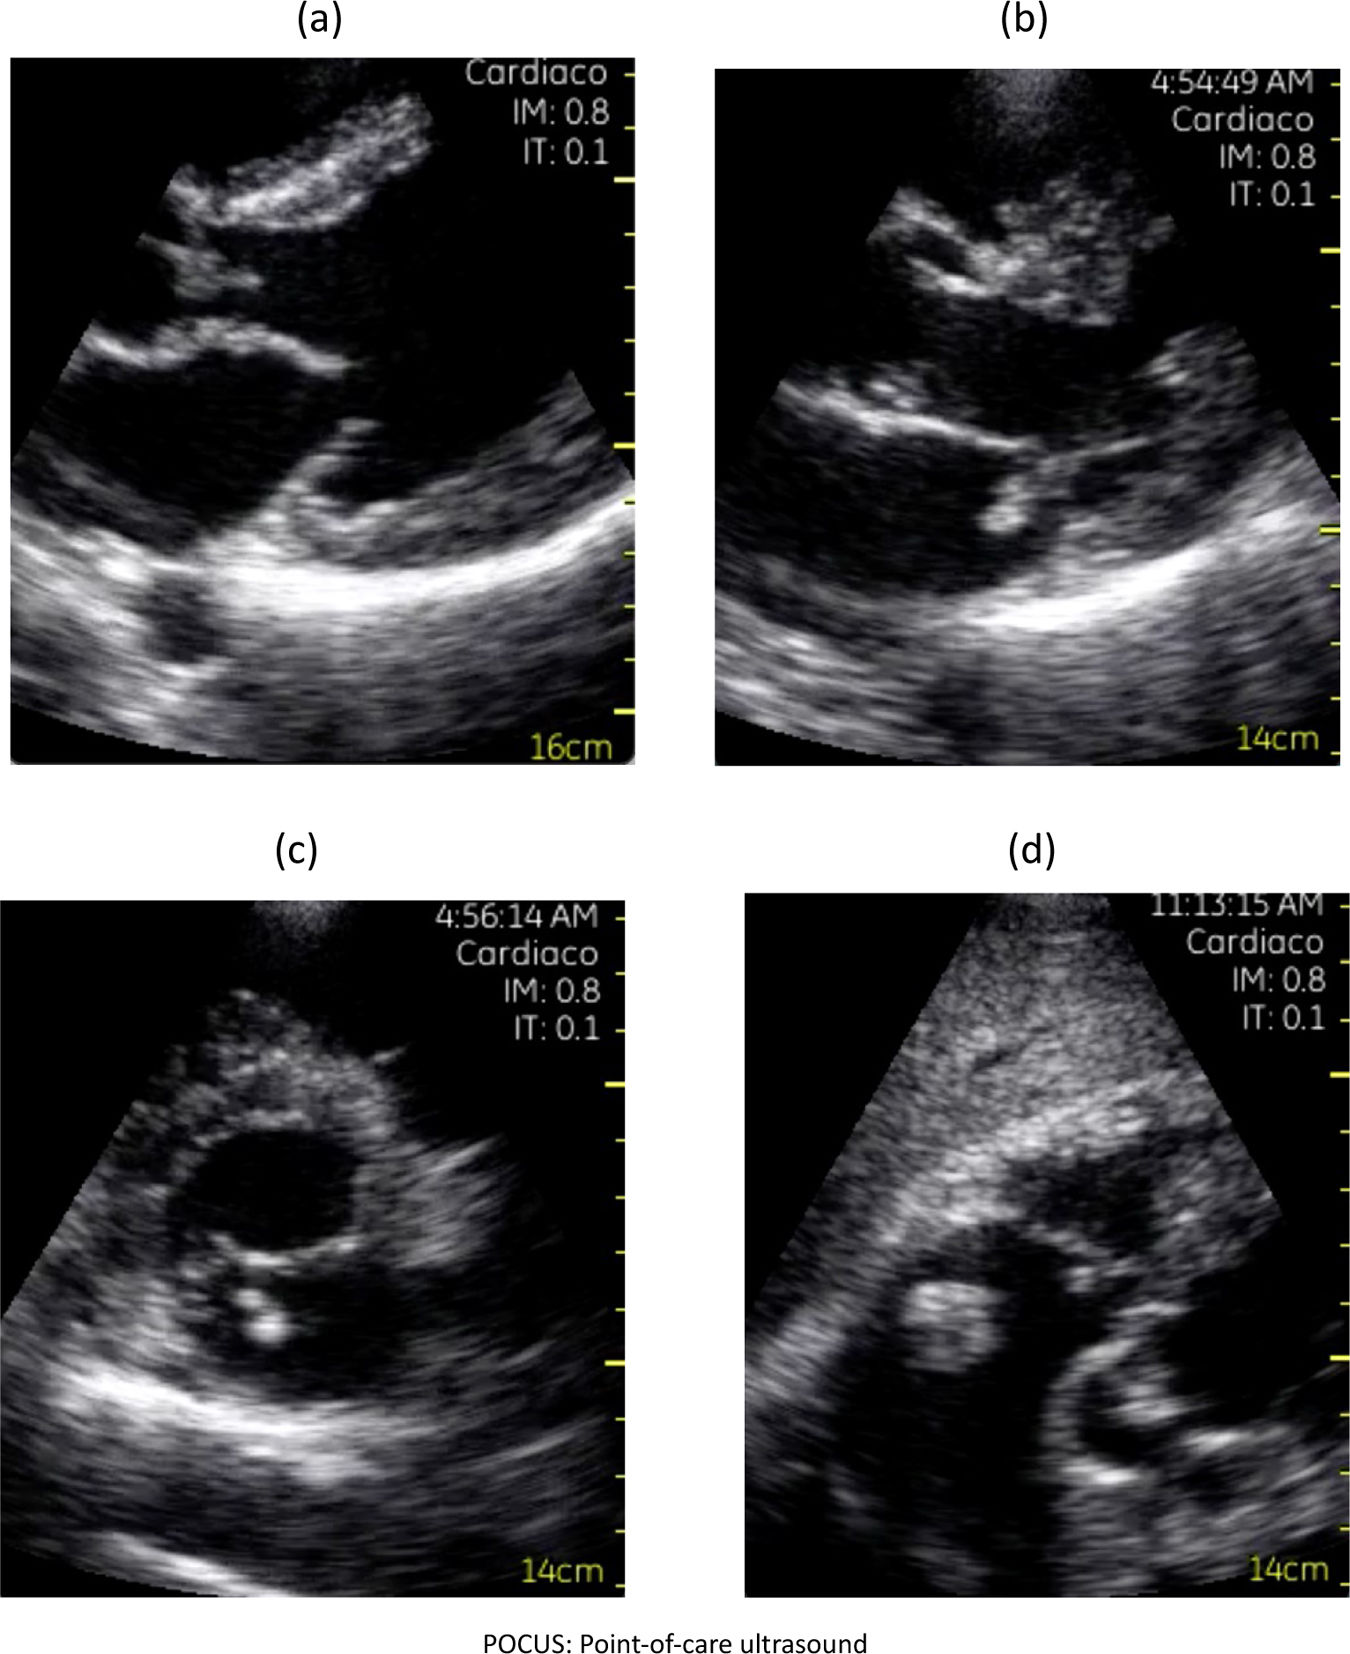

Más datosA narrative review assessed the utility of point-of-care ultrasound (POCUS) in evaluating suspected infective endocarditis (IE). MEDLINE, EMBASE, and Google Scholar were searched for studies published from January 1, 2010 to January 31, 2025. Data extraction was performed independently by three authors. Thirty-five studies involving 293 participants were included, the majority being case reports. For detecting valvular vegetations, POCUS demonstrated a sensitivity of 77% and a specificity of 94%. POCUS may serve as a useful adjunct to bedside physical examination, facilitating the detection of echocardiographic findings suggestive of IE and other endovascular infections. Nonetheless, the predominance of case reports, which represent the lowest level of clinical evidence, substantially limits the external validity and generalizability of these results. Further high-quality studies are warranted to confirm the diagnostic performance and clinical impact of POCUS in this setting. Overall, POCUS shows promise but evidence remains limited by study design.

Se realizó una revisión narrativa sobre la utilidad del ultrasonido en el punto de atención (point-of-care ultrasound [POCUS]) en pacientes con sospecha clínica de endocarditis infecciosa (EI). Se buscaron estudios publicados entre el 1 de enero de 2010 y el 31 de enero de 2025 en MEDLINE, EMBASE y Google Scholar. Tres autores extrajeron los datos de forma independiente. Se incluyeron 35 estudios con 293 participantes, la mayoría reportes de casos. POCUS mostró una sensibilidad del 77% y una especificidad del 94% para detectar vegetaciones valvulares. Como herramienta complementaria a la exploración física a pie de cama, POCUS puede facilitar la identificación de hallazgos ecocardiográficos sugestivos de EI y otras infecciones endovasculares. Sin embargo, el predominio de reportes de casos, que representan el nivel más bajo de evidencia clínica, limita considerablemente la validez externa y la generalización de los resultados. Se requieren estudios de mayor calidad para confirmar estos hallazgos.